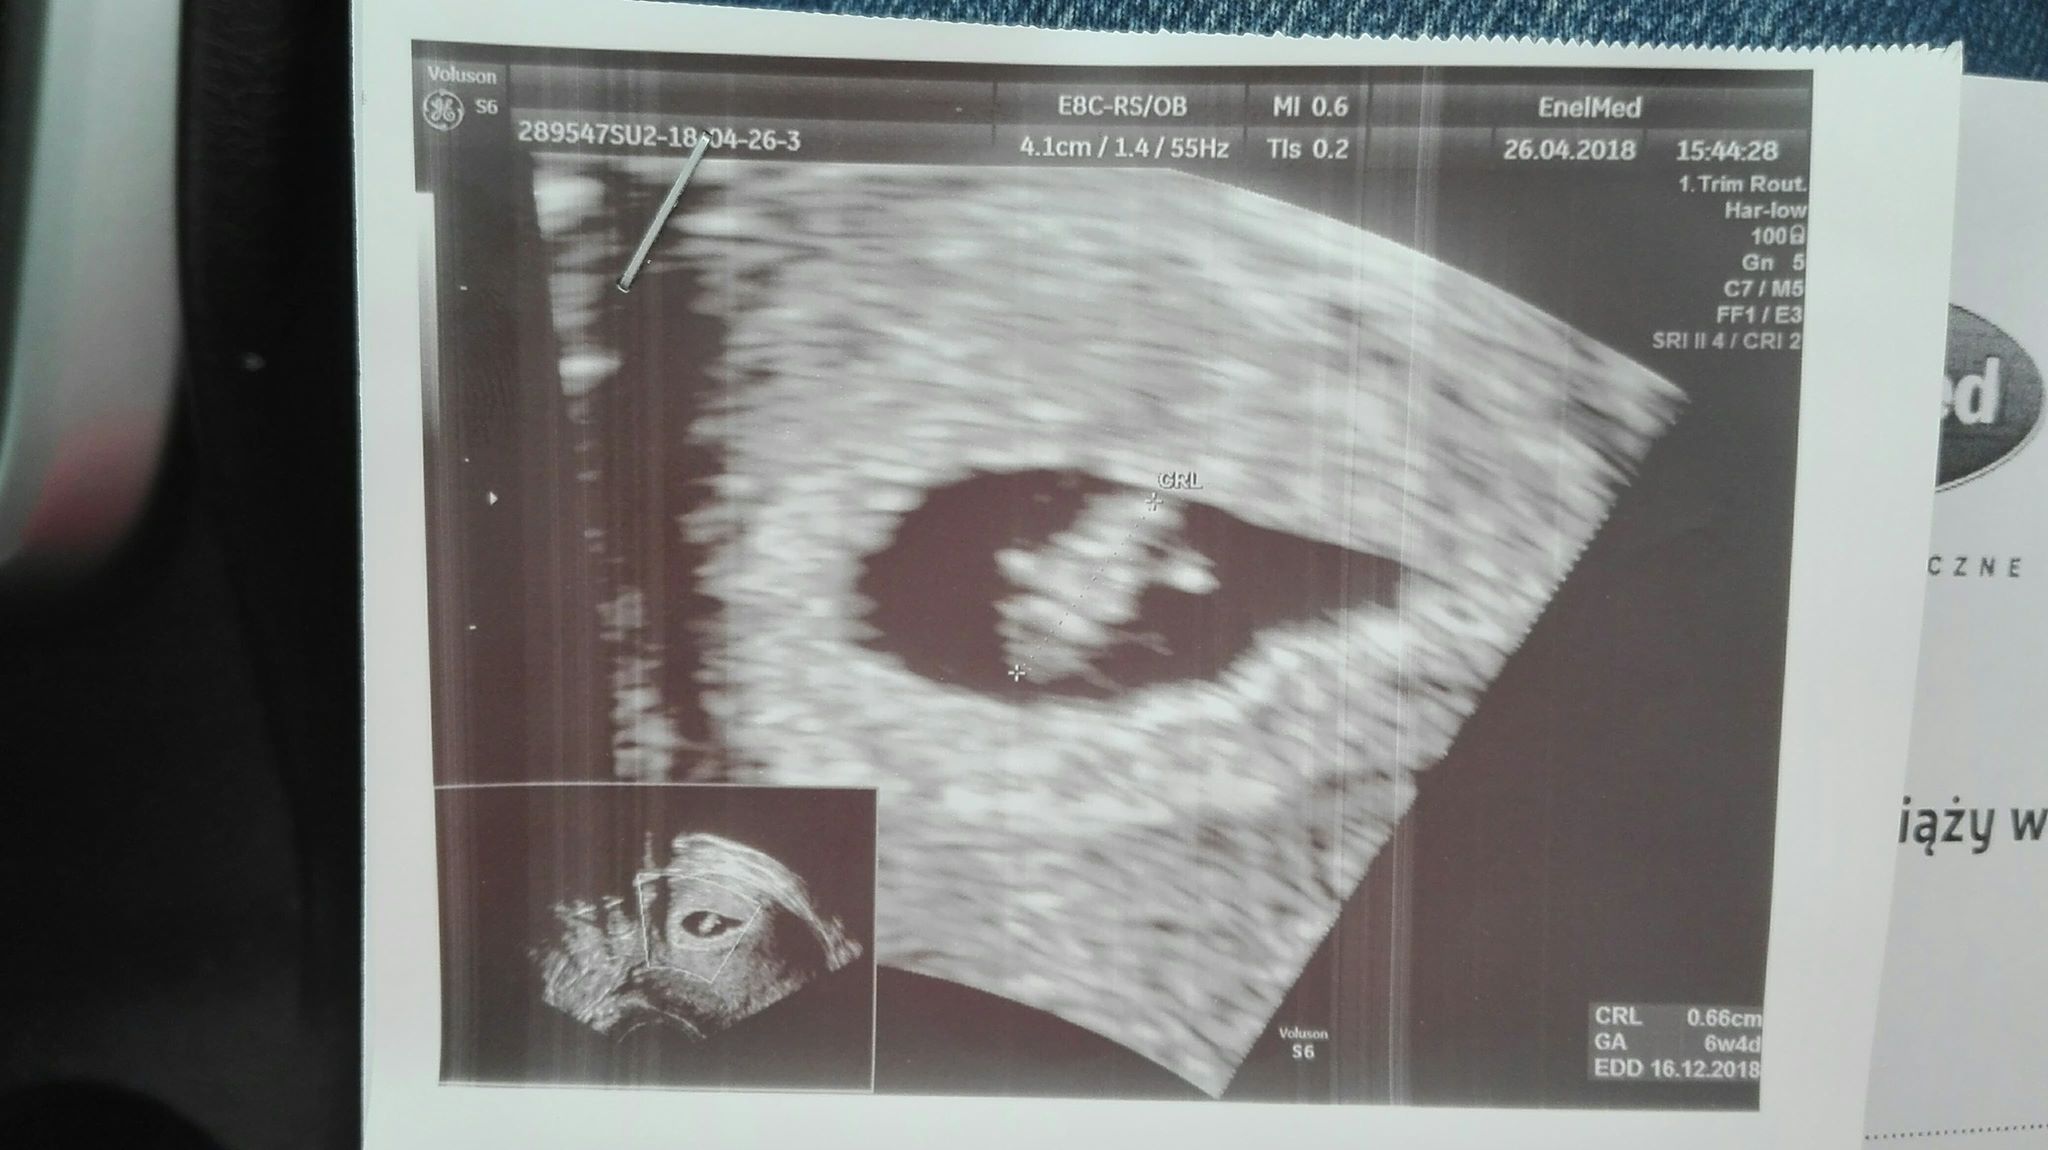

Witam, po wczorajszym USG jestem w najszczęśliwszej 6+4 tygodniowej ciąży, wczoraj dzidziuś miał całe 6,6mm i widzieliśmy jak serduszko bije! 160/min.

Termin porodu - 16.12 (może się pospieszy i 12.12 będę miała urodzinowy prezent?:)